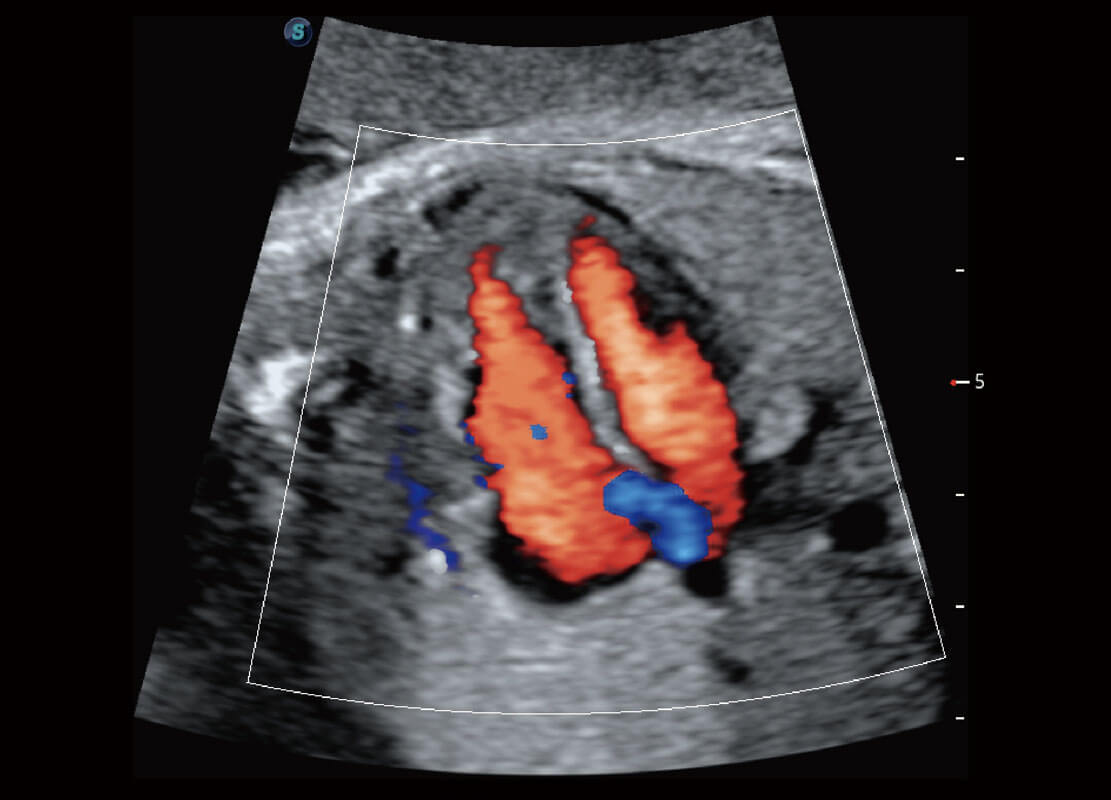

胎儿体循环

P60搭载一系列胎儿心脏成像技术,实现精细的胎儿心脏评估。

四腔切面

四腔心血流